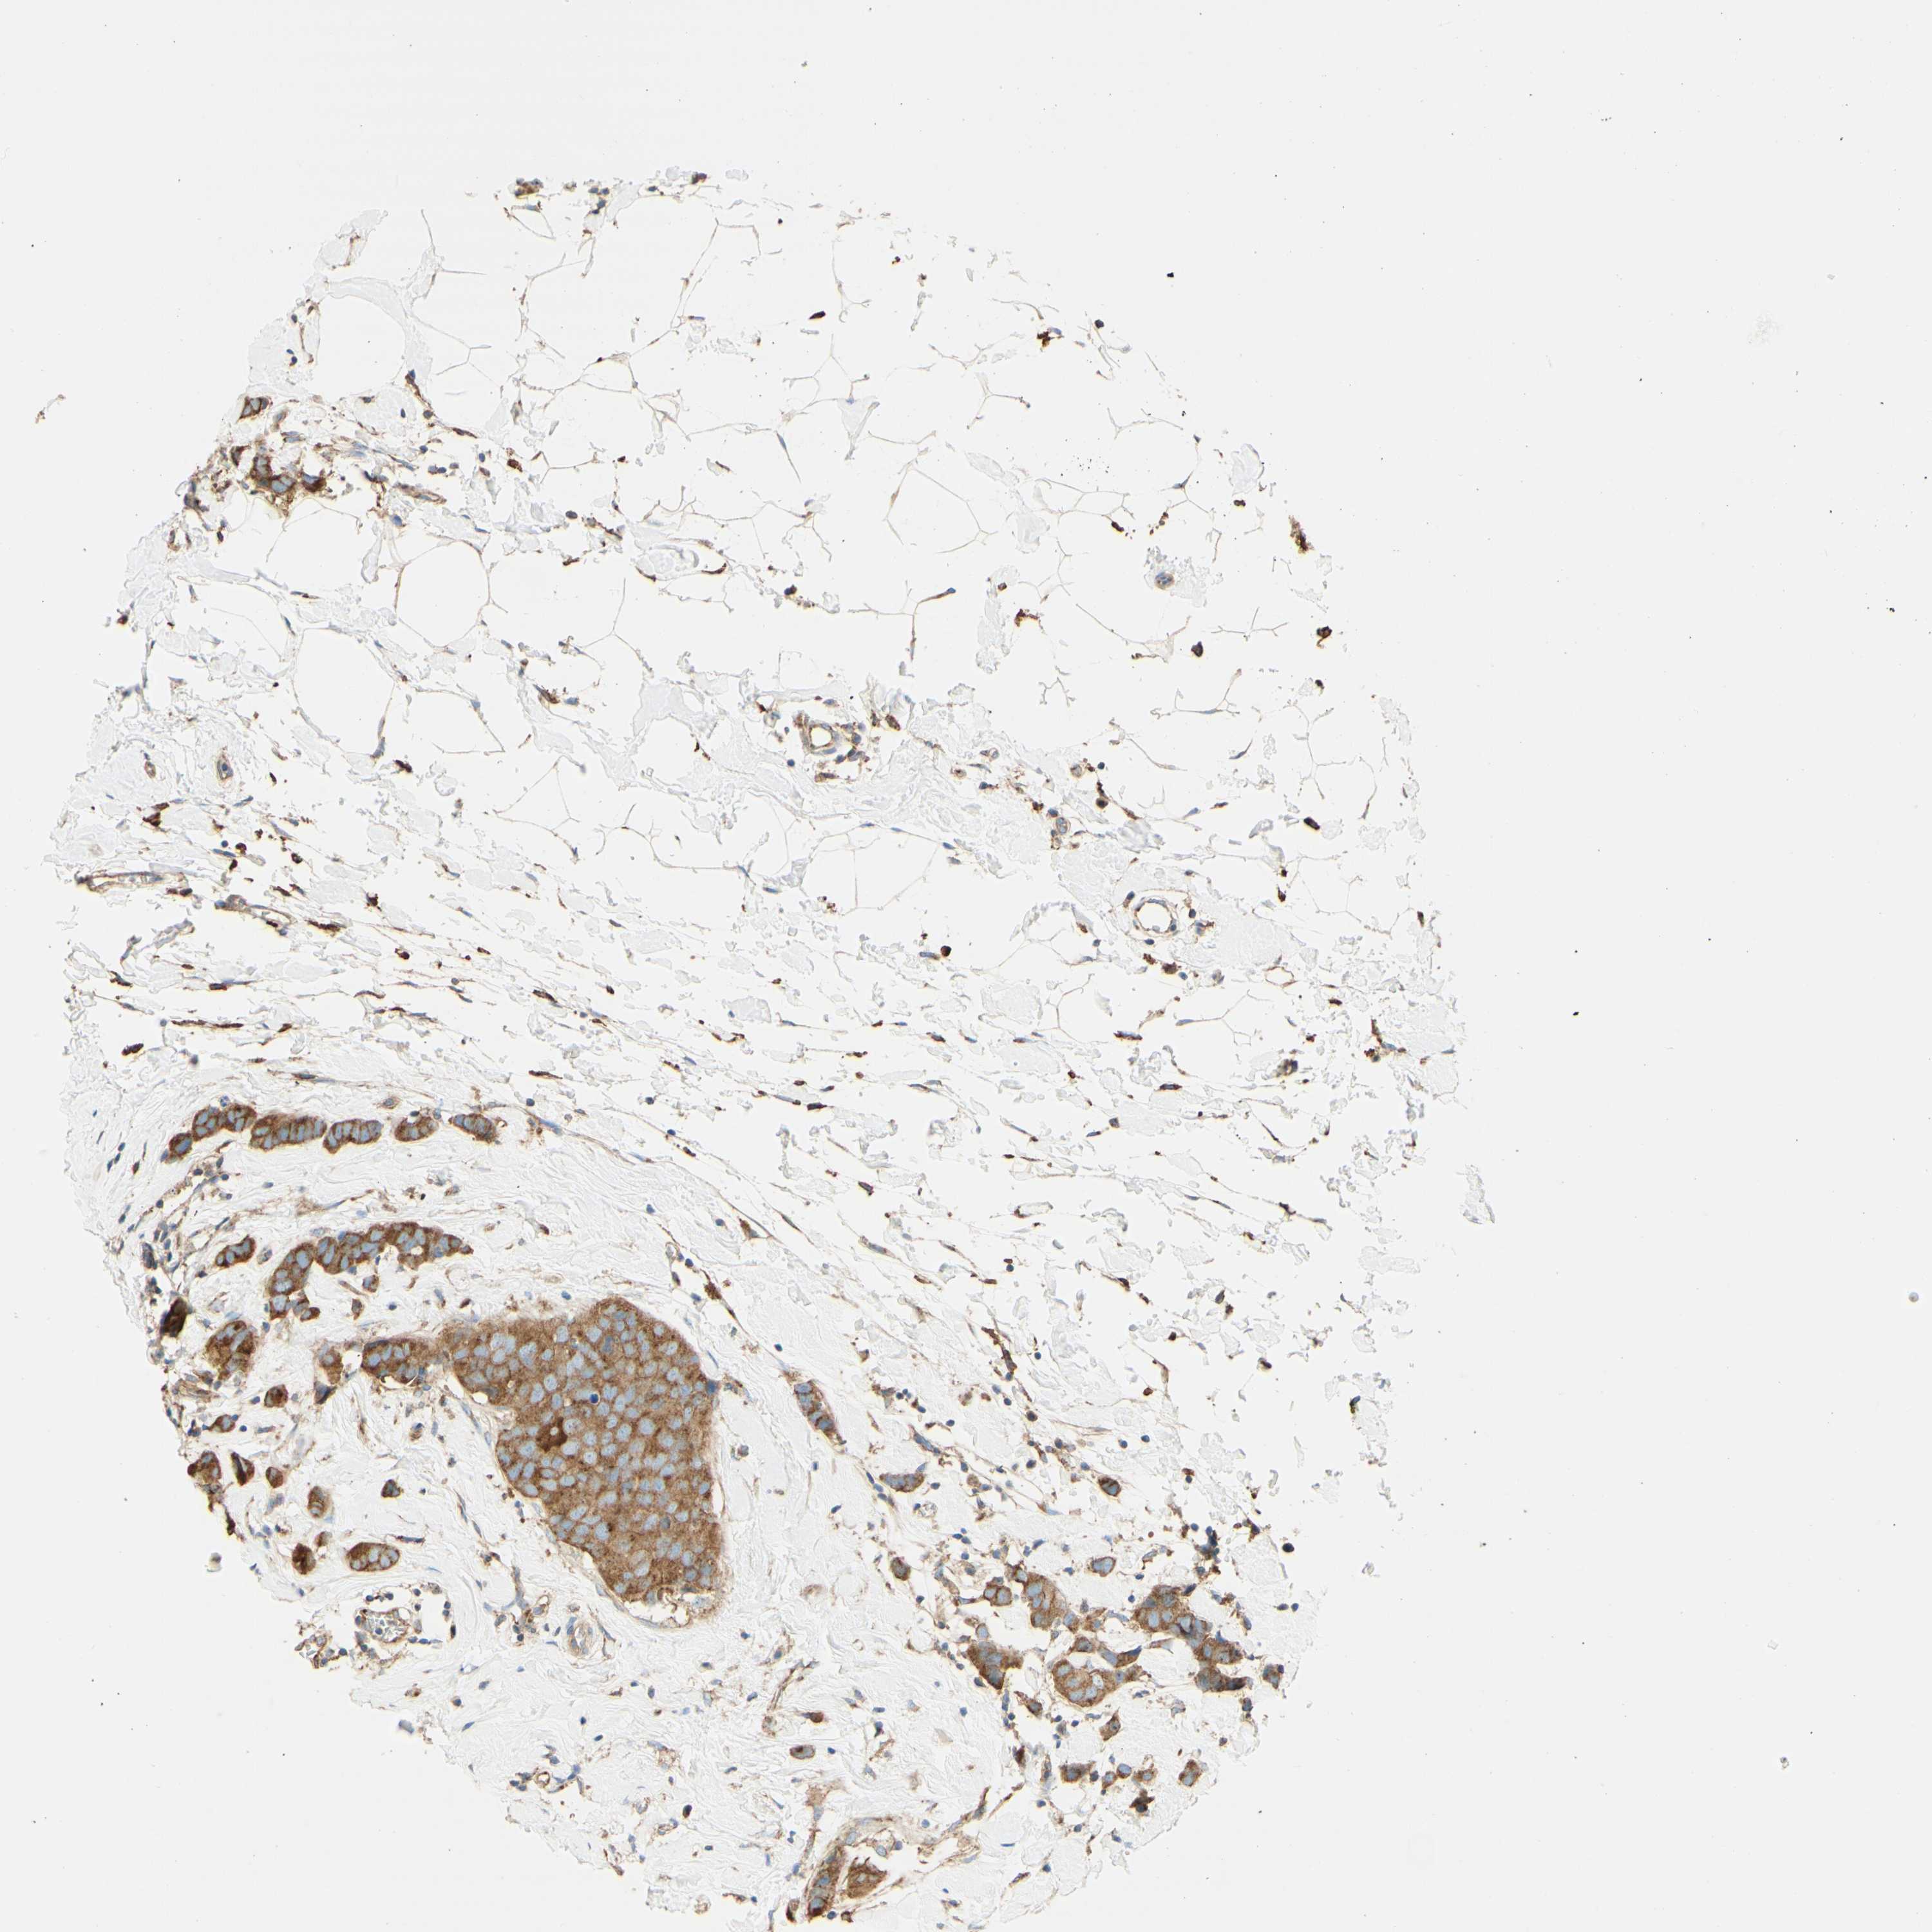

CANCER BREAST CANCER Show tissue menu

BRCA TCGA BRCA VALIDATION PROTEIN EXPRESSION